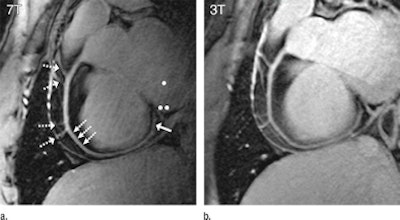

| Right coronary artery images in a healthy 26-year-old male show high visual vessel definition (dotted arrows) in the 7-tesla image (a) compared to 3 tesla (b). At 7 tesla, contrast is limited between the myocardium and the blood pool. Multiple right coronary artery side branches (dashed arrows) and distal parts of the RCA (solid arrow) are depicted clearly at both field strengths. |

Based on the images, van Elderen and colleagues concluded that quantitative parameters related to image quality attained at 7-tesla MRI equaled or surpassed those from 3-tesla in the 10 healthy young adult volunteers.